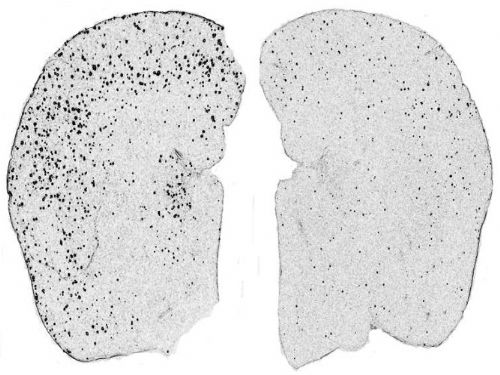

▶ 알츠하이머 모델 마우스의 뇌 절편. IL_12/23 분자가 결핍되거나 또는 신호경로가 감소되면 알츠하이머-유사 병리소견이 감소된다. 사진의 베타 아밀로이드(검은점) 판이 감소되었다. 좌측은 알츠하이머 마우스의 뇌 반구, 우측은 IL-12 수용체가 없는 알츠하이머 마우스의 뇌 반구, 아밀로이드가 65% 정도 감소하였으며, 인지능력저하가 감소되었다. |

그 결과, 사이토카인인 인터류킨(IL)-12와 23의 구성성분인 p40가 차단되었을 때, 아밀로이드 베타가 약 65% 감소함을 보여주었다.